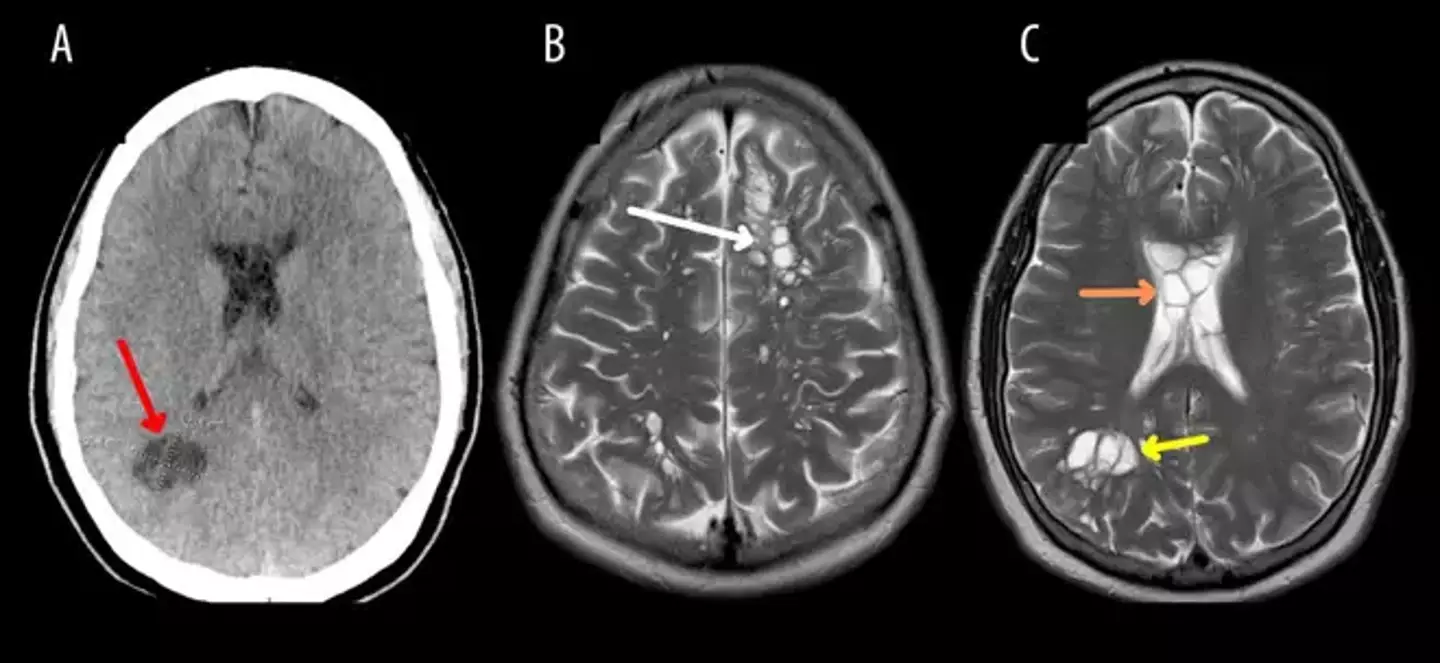

Medics then carried out a CT scan on the man, where they chillingly found a flurry of tapeworm larval cysts in his brain - which can cause cysticercosis.

After quizzing the patient, doctors concluded that he had contracted the tapeworm cysts because of 'improper handwashing' - having got the initial tapeworm from undercooked bacon. Yikes.

According to an article published in the American Journal of Case Reports discussing the man's illness, he also 'admitted to a habit of eating lightly cooked, non-crispy bacon for most of his life'.

The doctors who saved his bacon said he was discharged after two weeks while showing a 'regression' in lesions on his brain and an improvement in his headaches.